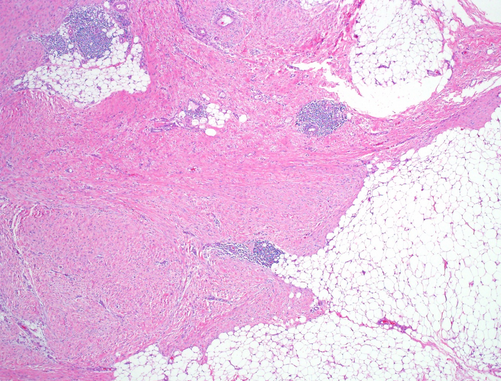

Painful, well circumscirbed skin lesion. Higher power magnification:

Angioleiomyoma

Well-circumscribed tumour.

Bundles of cytologically bland smooth muscle cells growing concentrically around blood vessels of varying calibre.